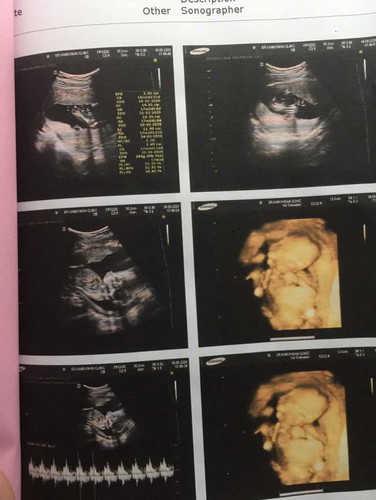

ซาวด์4มิติ กี่วิค ถึงจะเห็นหน้าลูกชัด ๆค่ะ ???

นี้เราซาวตอน4เดือน ค่ะ. วันที่15 มิถุนายนนี้ เราไปซาว ครบ22วิค อยากรู้ว่าจะเห็นหน้าลูกมั้ยค่ะ ตื่นเต้น ขอดูแม่บ้านอื่นหน่อยค่ะ. ขอบคุณค่ะ. #ทีมตุลาคม63

หมอเคยบอกว่าช่วงที่เหมาะแก่การซาวด์ 4 มิติคือ 28 สัปดาห์ค่ะ เราก็ซาวด์ 28 สัปดาห์ แต่ลูกไม่ยอมให้เห็นหน้าเลยค่ะ นอนคว่ำหน้าตั้งแต่ต้นจนจบ สรุปไม่ได้เห็นหน้าลูก ไม่ได้รูปสักรูป เหมือนไปเสียค่าซาวด์ฟรีๆ 3 พันกว่า แม่เซ็งเลย☹️☹️

ซาวตอน 32 wค่ะ แต่ลูกไม่ค่อยให้ความร่วมมือเท่าไหร่ กระตุ้นอยู่นานมาก เลยได้ชัดสุดแค่นี้ค่ะ

คุณหมอแนะนำช่วง 28-32w ค่ะ จะชัดที่สุด ส่วนบ้านนี้ซาวด์ตอน 30w ถือว่าชัดนะคะแม่

อันบนซาวรพ.เอกชนที่ฝากครรภ์ ล่างซาวคลินิกนอกค่ะ คนชัดต่างกันนิดหน่อย

คุณหมอบอกว่าถ้าซาวน์ 4 มิติจะเห็นชัดสุดตอน 27-28 สัปดาห์ค่ะ

บ้านนี้ซาวดูตอน 28 สัปดาห์ หมอบอกเป็นช่วงเวลาที่เหมาะ

28-32 จะชัดกำลังดีค่ะ อยู่ที่น้องให้ความร่วมมือด้วยค่ะ^^